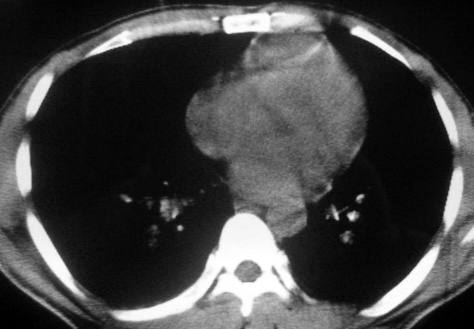

男,36岁,一月前醉酒淋雨后发热咳嗽,气短进行性加重.

抗生素治疗无效,痰检(一).

影像诊断:结核? 还有其他考虑吗?

双肺内中部见略不对称性蝶翼状高密度区,边界不清,部分呈磨玻璃样密度,并可见含气支气管征。肺门、纵隔内未见肿大淋巴结影。无胸腔积液。

考虑:1、肺炎,建议进一步查冷凝集试验除外支原体肺炎;

2、不除外霉菌感染。

双肺斑片状密度均匀病灶,边界模糊可见充气支气管征,上野多于下野,不支持结核,1肺内感染,2查肾功,中心型肺水肿待除外.

双肺中上野对称分布蝶翼样不均匀密度增高影,有支气管充气征,纵隔未见肿大淋巴结,发病突然,抗炎治疗无效,还是要考虑结核。

还是考虑肺水肿!蝶翼征.肺门增大,肺血管影增粗,!!病变累及中内带为主!要排外支原体感染.

支持: 双肺内中部见略不对称性蝶翼状高密度区,边界不清,部分呈磨玻璃样密度,并可见含气支气管征。肺门、纵隔内未见肿大淋巴结影。无胸腔积液。